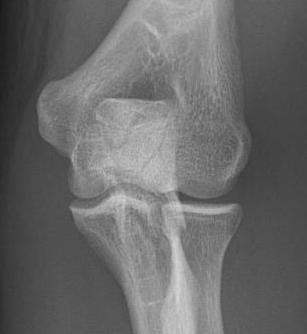

Mayo Classification

A: Non comminuted

B: Comminuted

| Type I | Type II | Type III |

|---|---|---|

| Minimally displaced | Displaced | Trans-olecranon fracture dislocation |

| 10% | 85% | 5% |